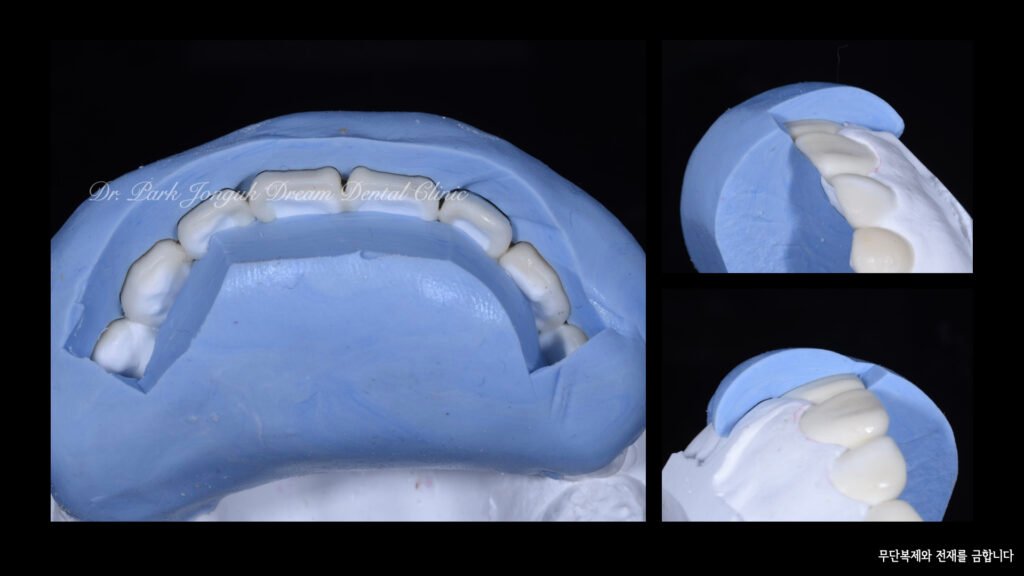

사진 8~10 — 최종 라미네이트 제작

드림치과에서는 ‘빌드업(Hand-Layered)’ 방식을 적용합니다.

단일 세라믹이 아닌 여러 종류의 세라믹을 층층이 쌓아

자연치아 고유의 깊이감과 투명한 끝부분을 재현합니다.